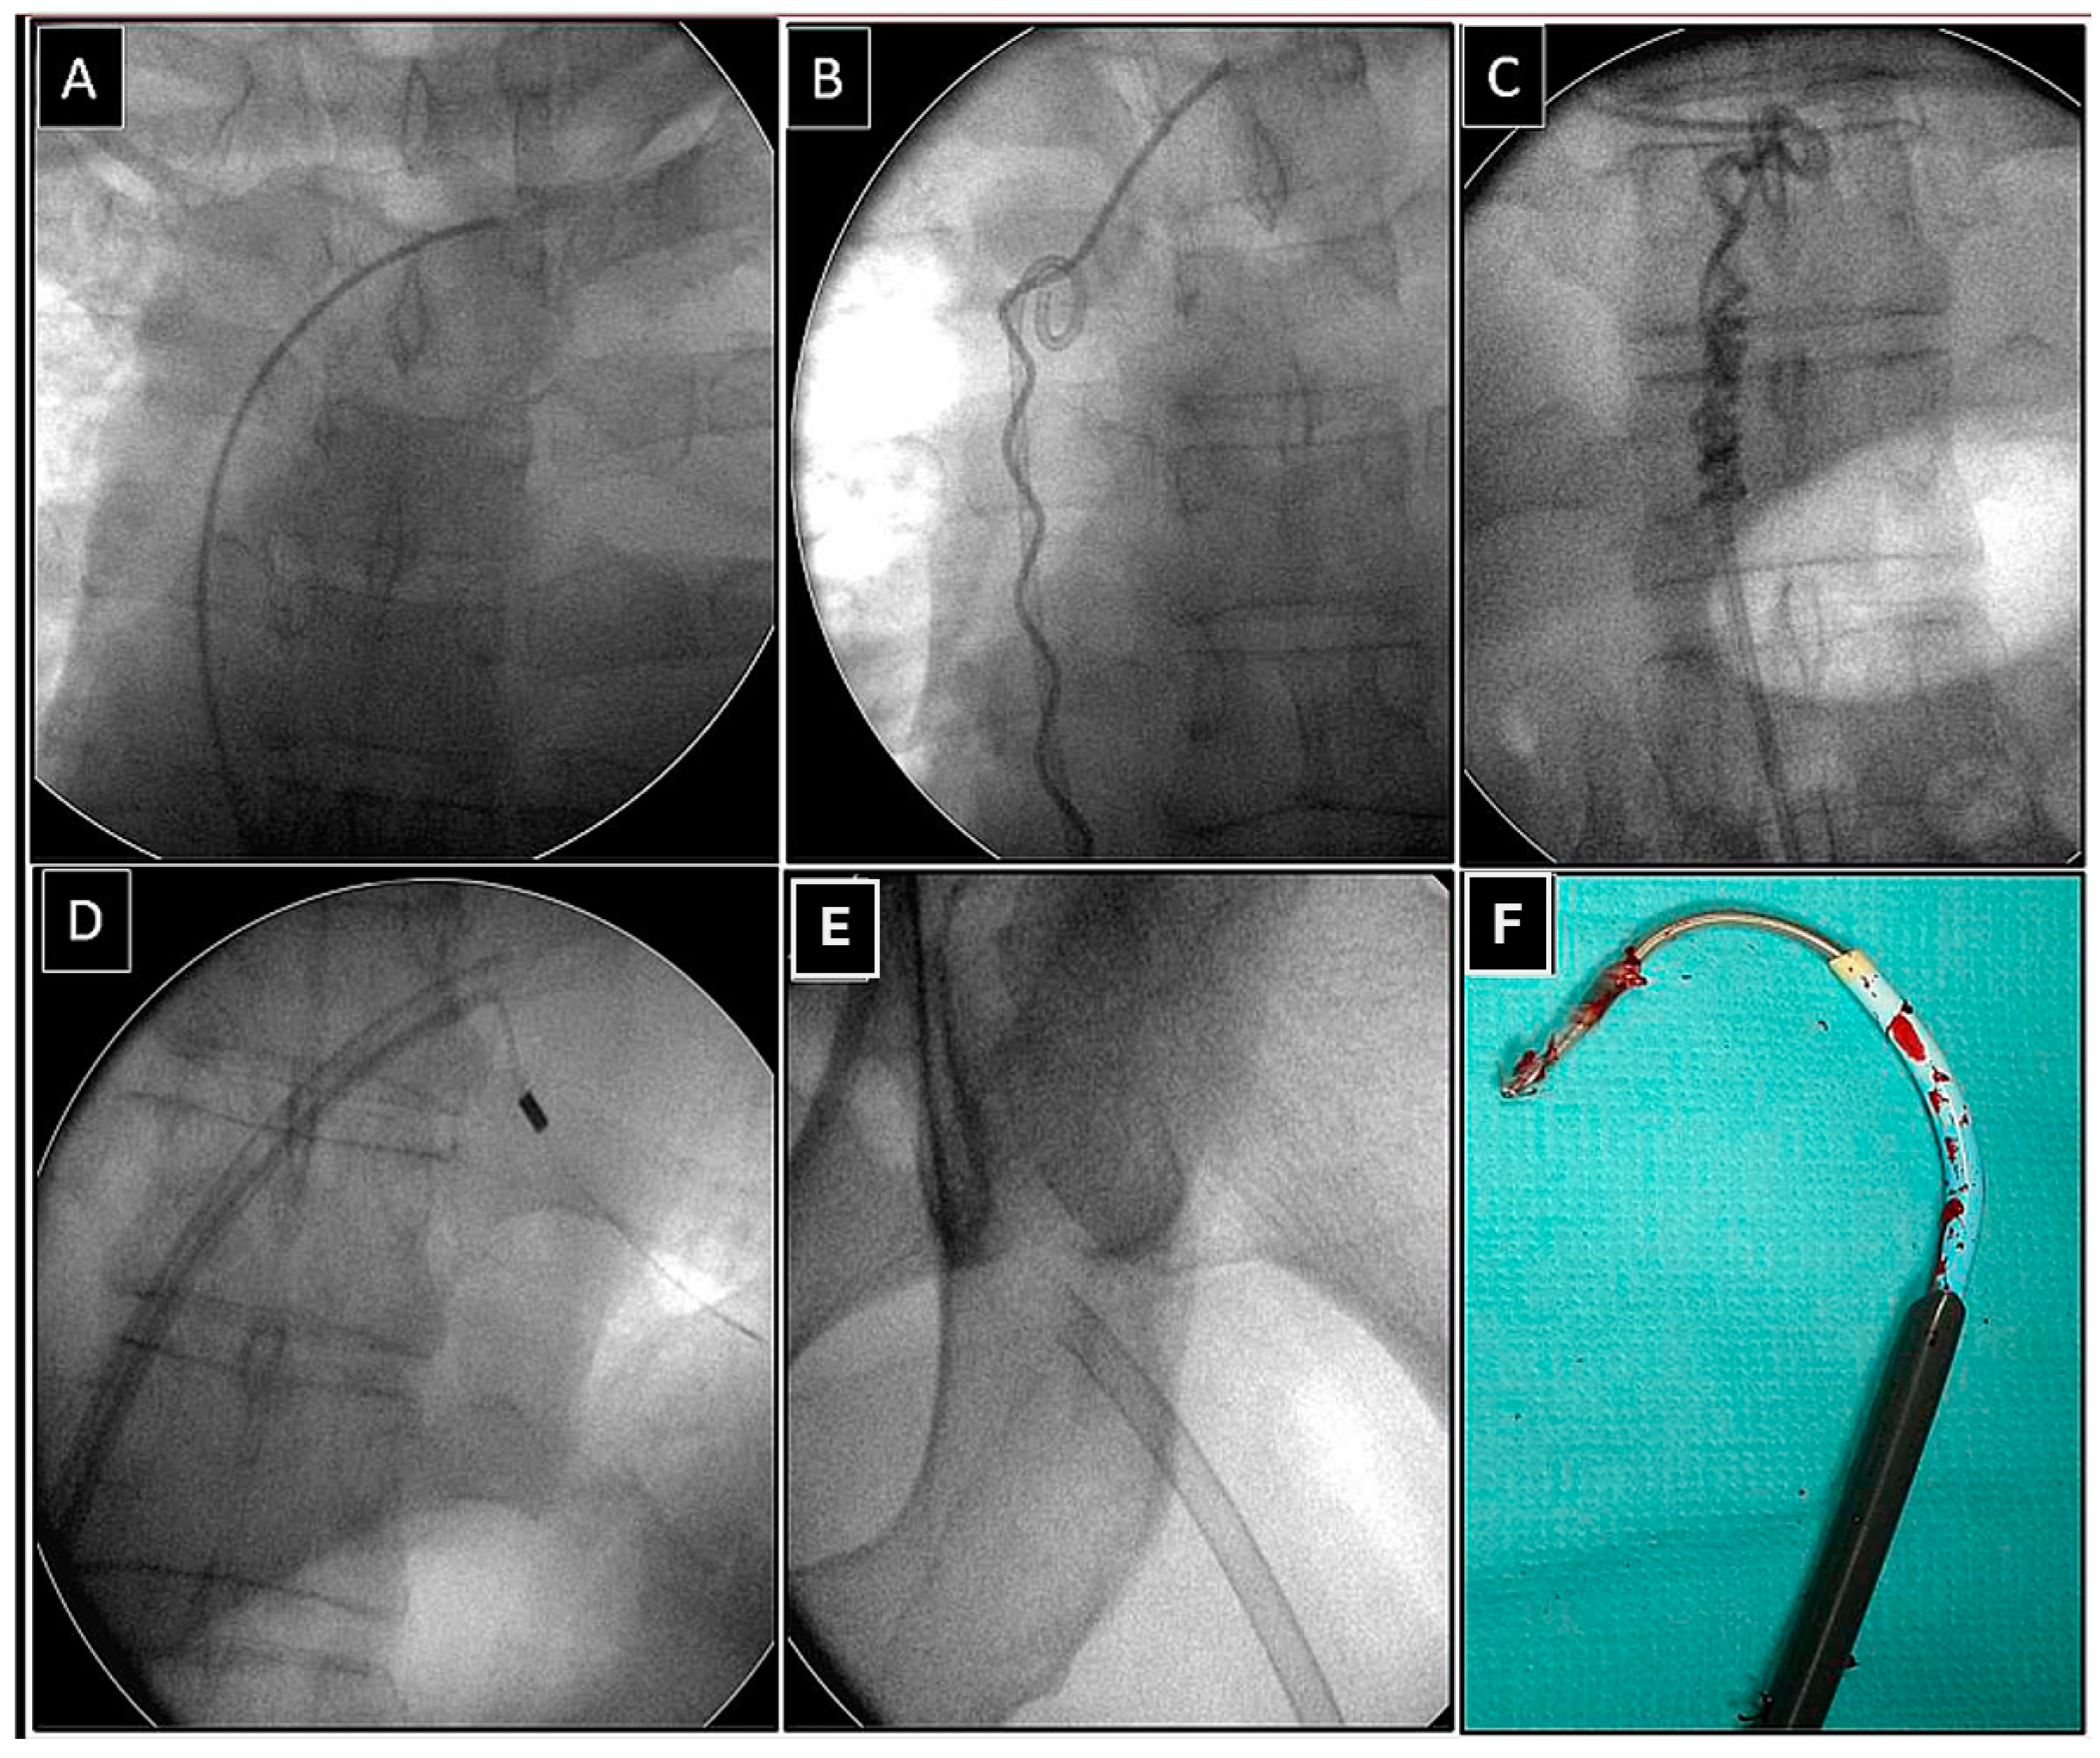

Extraction of Leads with Migrated Proximal Ends into the Cardiovascular Space

- Removal of such leads requires the use of different approaches and dedicated and non-dedicated tools.

| Superior approach | 6 (15.39) | 3 (23.08) p = 0.832 | 3 (23.08) p = 0.832 | 5 (71.43) p = 0.007 | 17 (23.61) |

| Combined approach | 3 (7.69) | 3 (23.08) p = 0.316 | 1 (7.67) p = 0.548 | 1 (14.29) p = 0.874 | 8 (11.11) |

| Femoral approach | 29 (74.36) | 7 (53.85) p = 0.298 | 8 (61.54) p = 0.596 | 1 (14.29) p = 0.001 | 45 (62.50) |

| Lasso/basket in CS sheath and a polypropylene or rotational sheath over them (dilatation) | 13 (76.47) | Lasso/basket in CS sheath and a polypropylene rotational sheath over them—superior approach (dilatation) | 8 (100.0) |

| Lasso/basket in CS sheath—superior (pulling only) | 1 (5.88) | Lasso/basket in CS sheath—superior approach (pulling only) | 0 (0.00) |

| Lasso/basket only (pulling only) | 3 (17.65) | Lasso/basket only—superior approach (pulling only) | 0 (0.00) |

| Loop (pulling, end release) | 6 (35.29) | Loop femoral approach | 6 (75.00) |

| Pig-tail + winding and shifting superior approach (end release) | 3 (17.65) | Pig-tail femoral approach | 1 (12.50) |